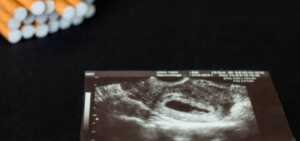

LES MÉTHODES DE SEVRAGE TABAGIQUE POUR FEMME ENCEINTE

Le tabagisme pendant la grossesse est la principale cause de morbidité et de mortalité obstétriques. Pourtant, 20 % des femmes enceintes en France continuent de fumer pendant leur grossesse.

Le tabagisme pendant la grossesse a de graves conséquences sur le développement fœtal. Premièrement, les bébés des mères fumeuses ne se développent pas aussi bien en raison du manque d’oxygène causé par la nicotine. La nicotine traverse le placenta et atteint directement le fœtus, se déposant non seulement dans le sang de la mère, mais aussi dans la muqueuse utérine, où sa concentration est 10 à 20 fois plus élevée que dans le sang.

Les poumons du bébé stockent également les toxines contenues dans la fumée. Les maladies dont souffrent les bébés de mères fumeuses sont regroupées sous le terme technique de « syndrome du tabac fœtal ».